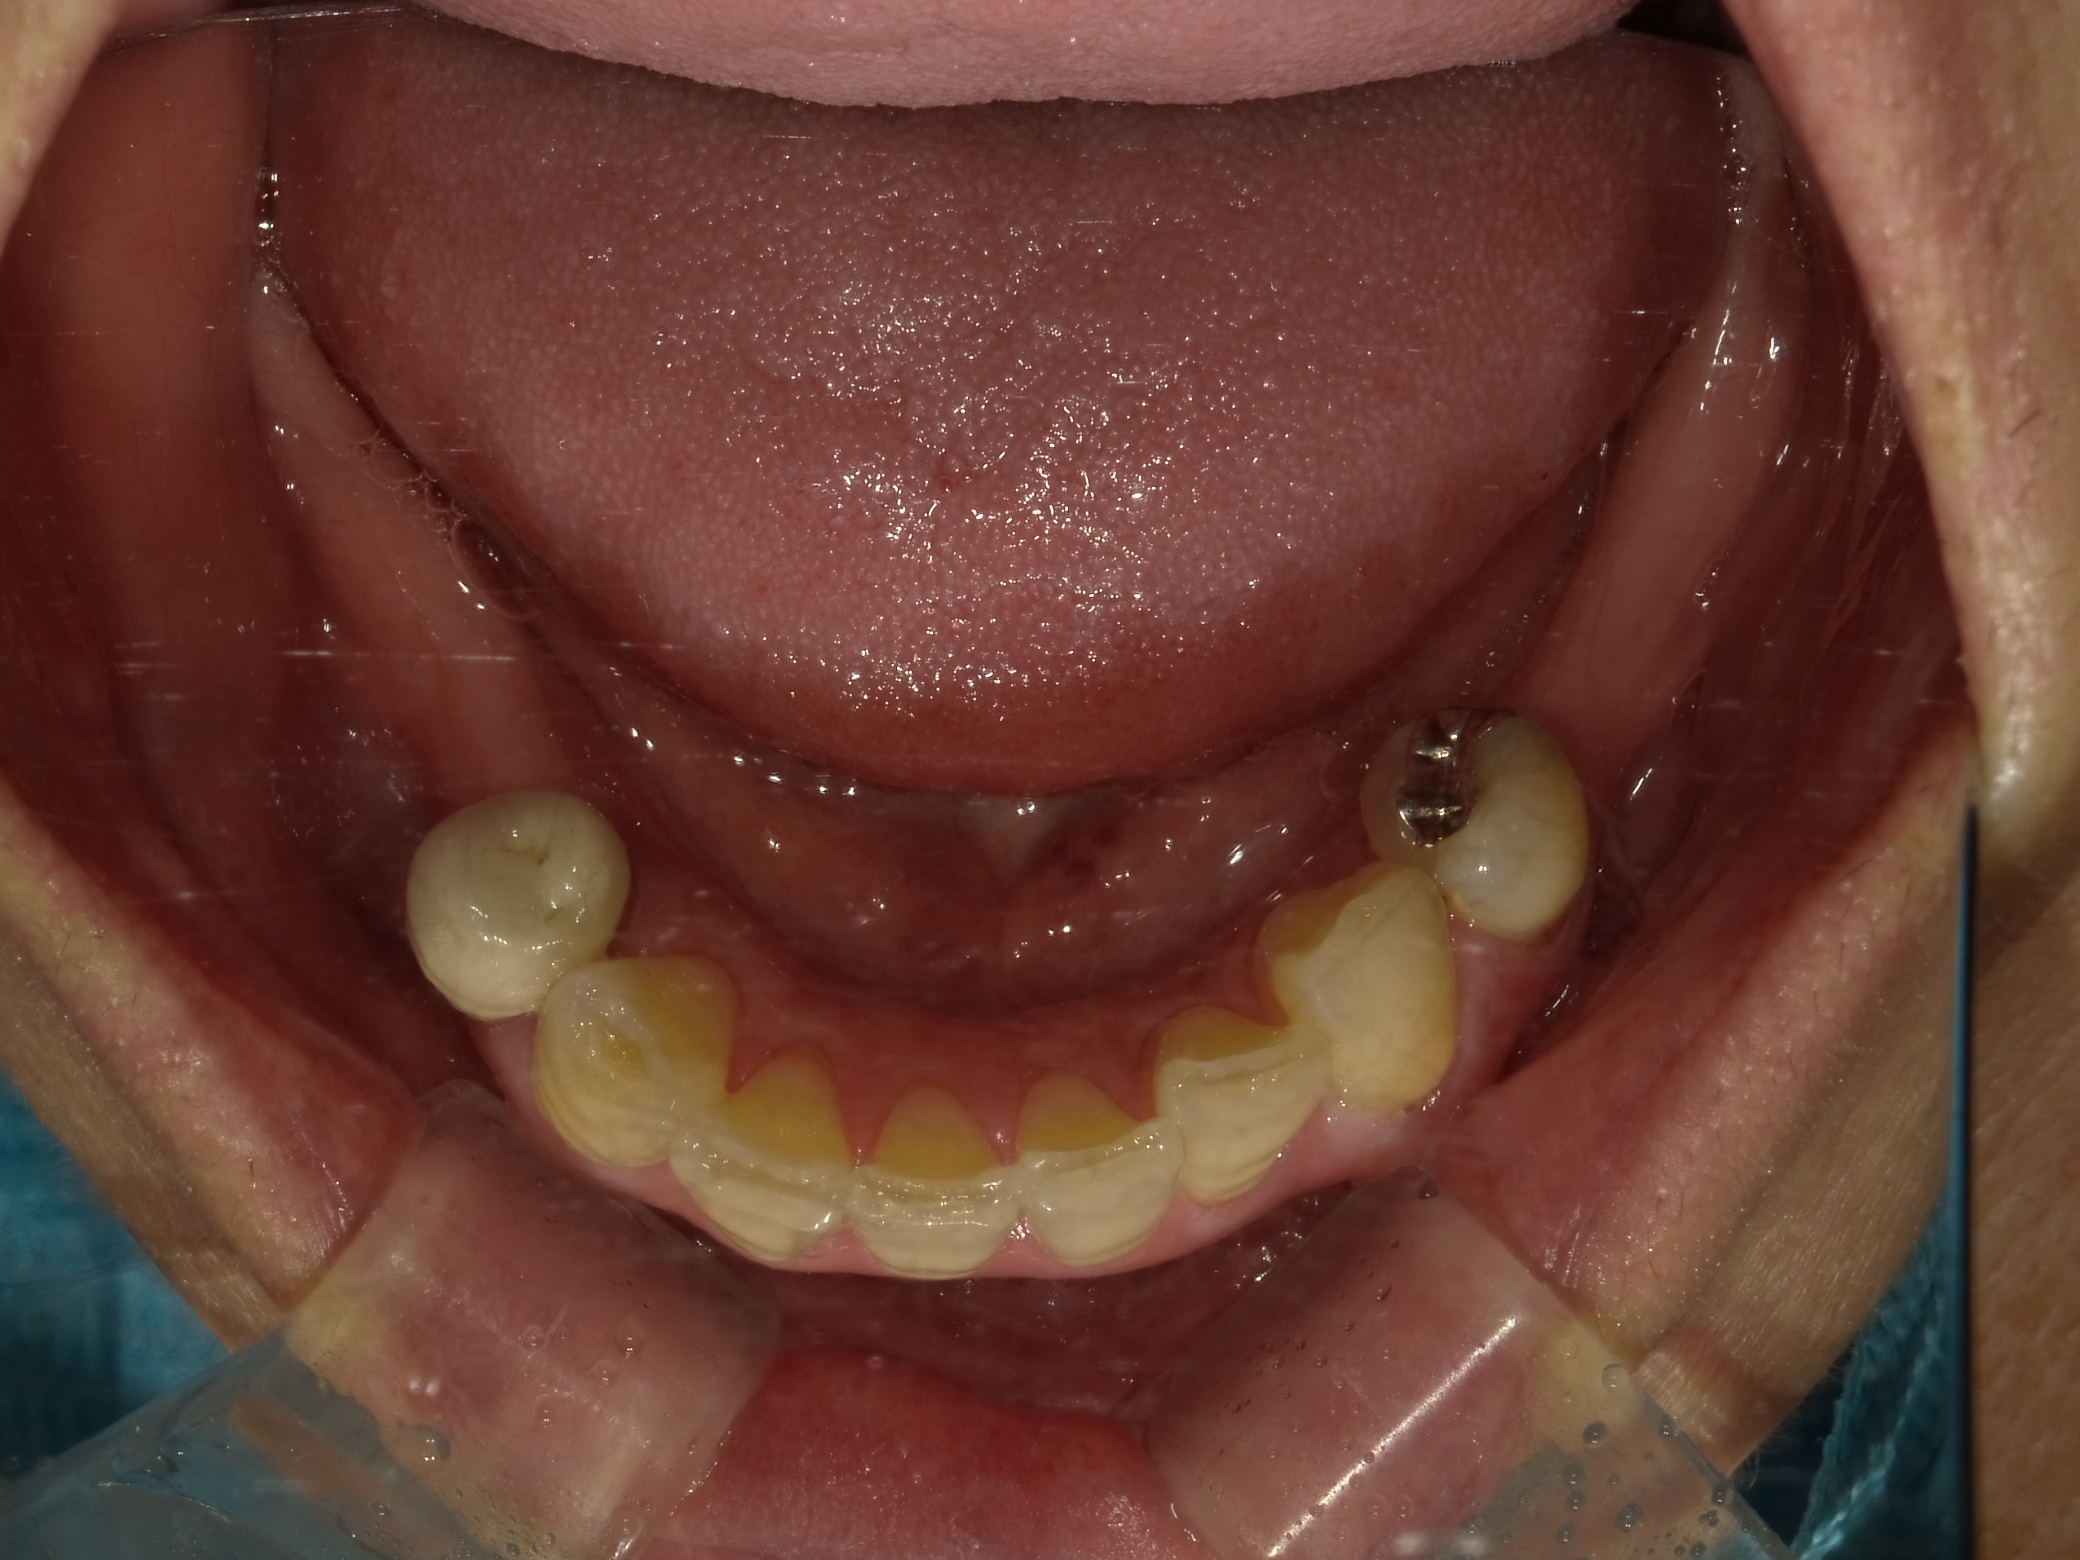

AFTER

主訴

全体的に見た目を綺麗にしたい。奥歯でしっかり噛みたい。

診断名・主な症状

臼歯部欠損

年齢

65歳

治療内容

インプラント埋入(左下5・6,右下5・6,左上4・6)

サイナスリフト(左上4・6)

ジルコニアBr(右上6−左上3)

E –MAX CAD(右下4)

セラミックインレー(左下4)

治療期間/

約1.5年/約20回

インプラント治療 約2,000,000円

その他被せ物治療など 約1,000,000円

合計 約3,000,000円